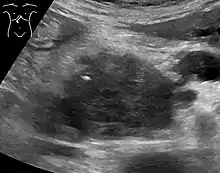

Medical imaging techniques, such as computed tomography (CT scan) and endoscopic ultrasound (EUS) are used both to confirm the diagnosis and to help decide whether the tumor can be surgically removed (its "resectability").[12] On contrast CT scan, pancreatic cancer typically shows a gradually increasing radiocontrast uptake, rather than a fast washout as seen in a normal pancreas or a delayed washout as seen in chronic pancreatitis.[56] Magnetic resonance imaging and positron emission tomography may also be used,[2] and magnetic resonance cholangiopancreatography may be useful in some cases.[32] Abdominal ultrasound is less sensitive and will miss small tumors, but can identify cancers that have spread to the liver and build-up of fluid in the peritoneal cavity (ascites).[12] It may be used for a quick and cheap first examination before other techniques.[57]

.jpg.webp)

A biopsy by fine needle aspiration, often guided by endoscopic ultrasound, may be used where there is uncertainty over the diagnosis, but a histologic diagnosis is not usually required for removal of the tumor by surgery to go ahead.[12]